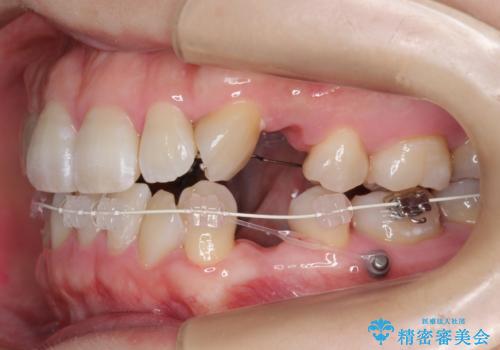

ハーフリンガル 犬歯のねじれ 歯根の外部吸収している歯を抜歯

- ハーフリンガル

レントゲンを撮影したところ、右下4は神経のない歯で、外部吸収といって、根がだんだん短くなり、やがて抜けてしまう症状になっていました。また、アンキローシスを起こしている可能性があるため、動かない可能性が高い状態でした。

矯正治療で右下を抜歯し、スペースを天然の歯でつめる矯正治療を行いました。

治療期間はかかりましたが、右下4が一生もつとは思えない状態でしたので、人工物を入れないようにすることができました。